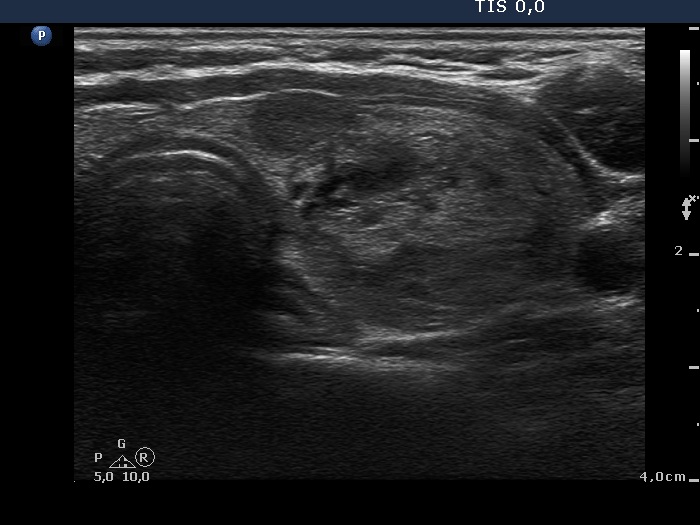

Palpation: multiple nodules were palpated. There was a large, firm nodule in the left lobe.

Ultrasonography: The thyroid was echonormal and contained several nodules with different echogenicities including a hypoechogenic one in the ventromedial part of the left lobe. This lesion presented a lobulated margin and a type 1 vascular pattern.